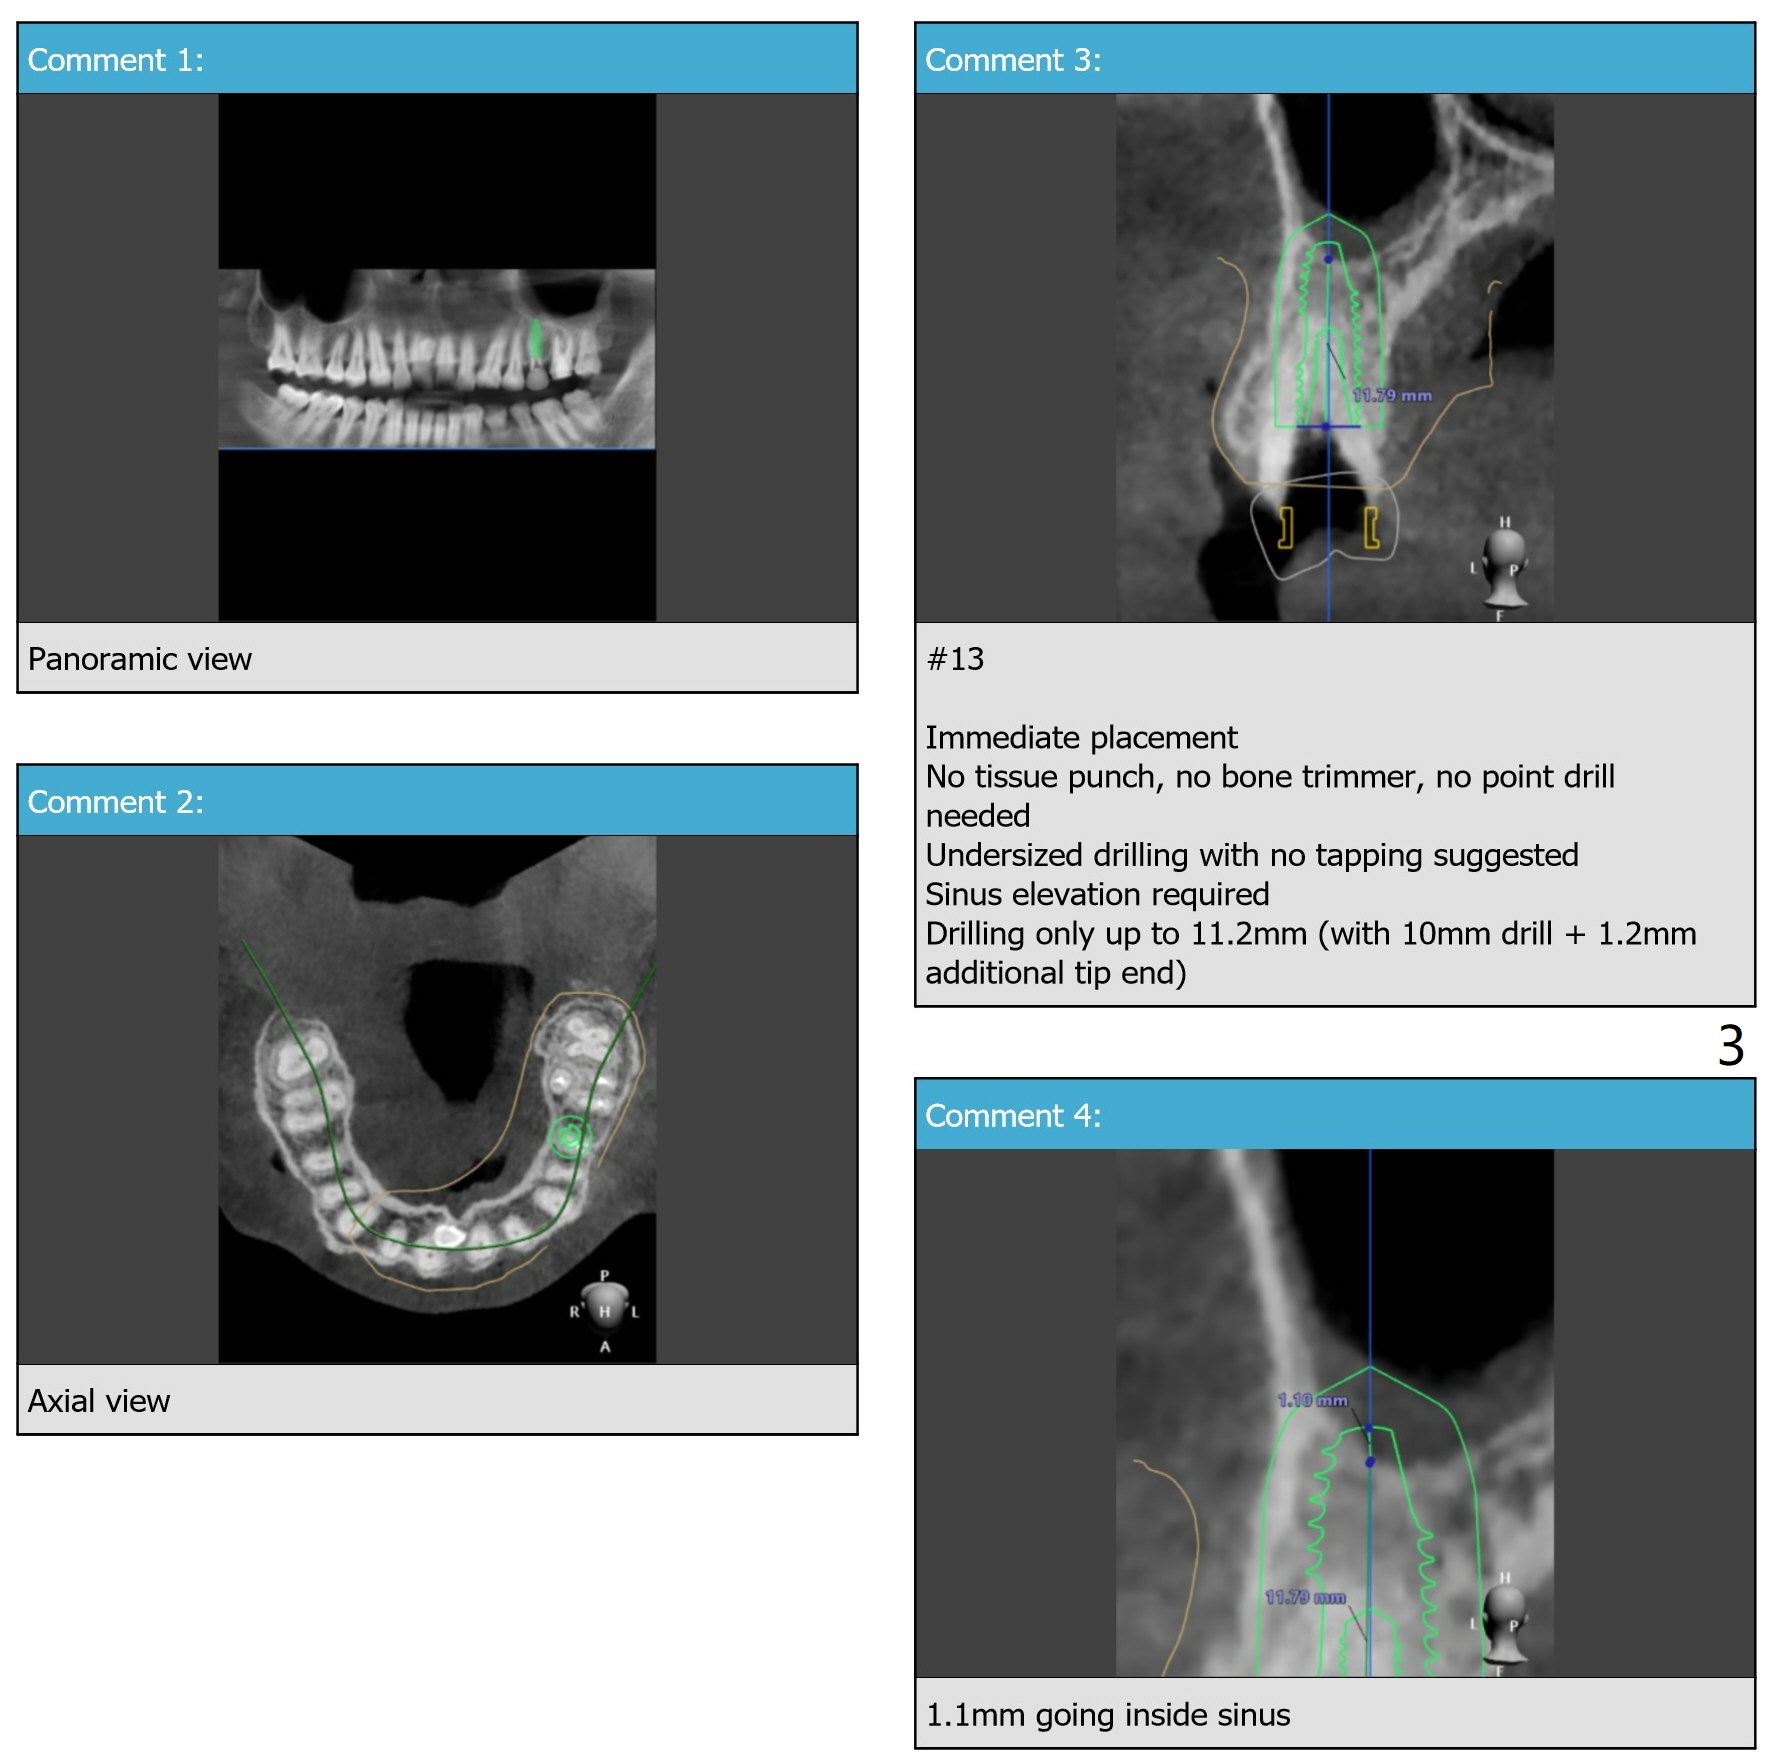

Underprep in Depth for Sinus Lift

After #13 implant placement, remove DO caries at #14 for composite and splinted provisional. Consider taking PA after 2.2 mm drill to depth because of the curved root of #12. Placee IBS implant with IS driver.

Return to Upper Premolar Immediate Implant, Trajectory II Clindamycin